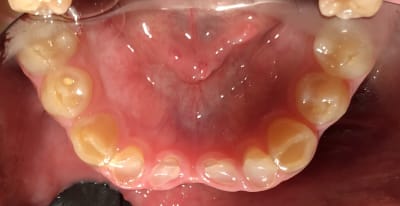

Bonjour je suis lenovo ici . Quelqu’un pourrait-il me donner toutes les étapes pour faire ce cas ? Que faut-il faire précisément ? Le patient n’a pas de contraintes financières. Pas de lésions apicales. Uniquement des usures de dents.

Les photos ne sont pas dingues, mais les usures semblent très majoritairement antérieures. Pourquoi?

Je suspecte un cas d'ortho non traité sous jacent XXL ... que j'aimerais voir sa télé de profil ...

Dentinogenèse imparfaite + bruxisme